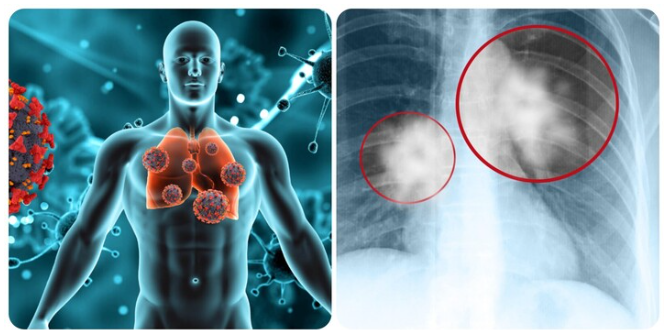

Ung thư phổi là một trong những căn bệnh ung thư nguy hiểm, nhận biết sớm dấu hiệu cảnh báo bệnh sẽ giúp cho việc điều trị thuận lợi hơn.

Ung thư phổi là một trong những căn bệnh ung thư nguy hiểm gây tử vong hàng đầu